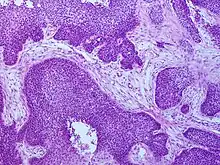

Diagnosis

Medical history, physical examination and medical imaging may suggest a squamous-cell carcinoma, but a biopsy for histopathology generally establishes the diagnosis. TP63 staining is the main histological marker for squamous-cell carcinoma. In addition, TP63 is an essential transcription factor to establish identity of the squamous cells.[18]